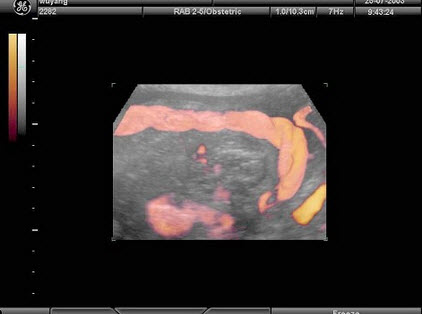

2、单项选择题

下图为宫内孕囊声像图,可见心管搏动,该胎儿至少大于多少周()

A.6周

B.9周

C.10周

D.12周

E.8周